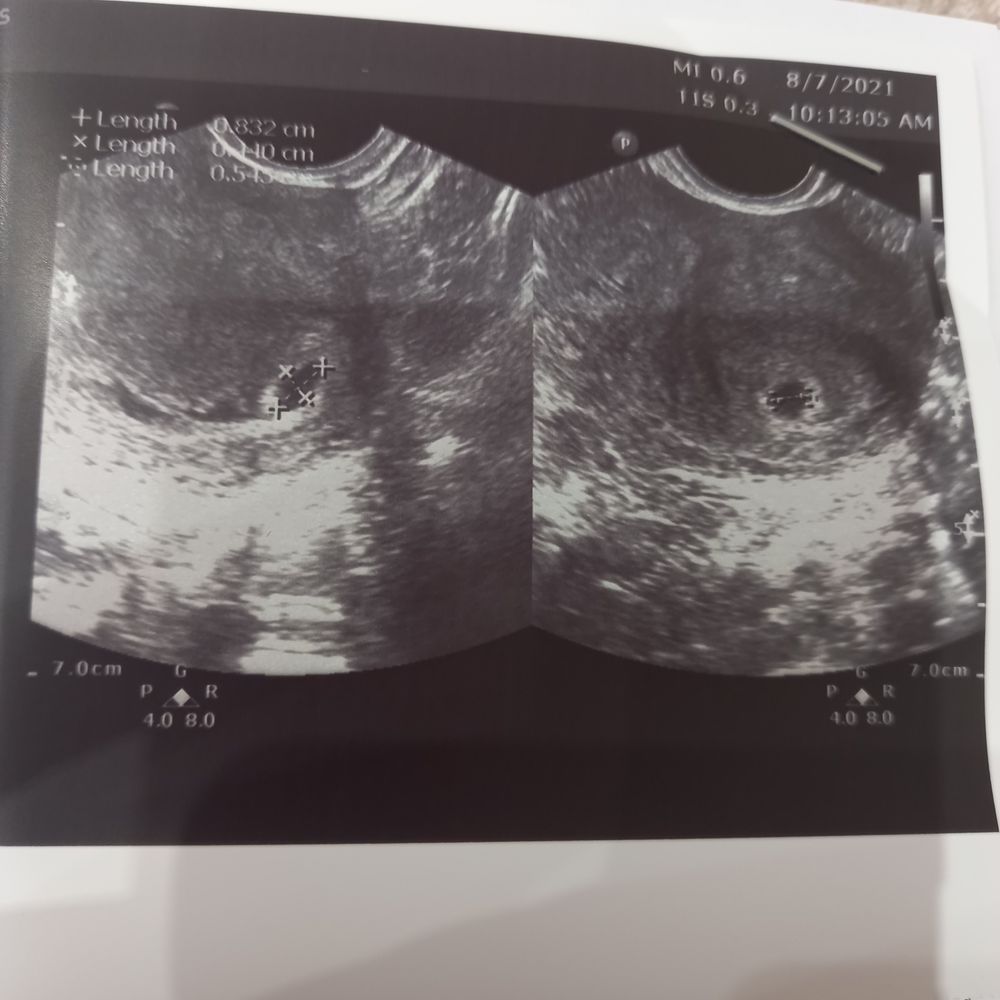

Первое узи

Поздравляю💐🎉 А какой срок у вас?) У меня в 5 недель ровно 2,7 мм нашли , совсем крошку.

Вера, по месячным 6 нед, но овуляция была поздняя на 20дц из 31. И если считать по овуляции то сегодня 5н2д.